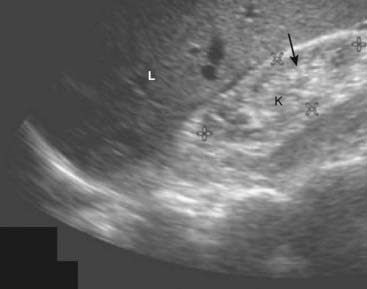

Urinary Tract

Normal Ultrasound Anatomy

image The kidneys normally measure 9-12 cm in length, 4-5 cm in width, and are 3-4 cm thick. The renal sinus is home to the renal pelvis and the major branches of the renal artery and vein. Because the renal sinus contains fat, it normally appears brightly echogenic. The calyces are normally not visible. The medullary pyramids are hypoechoic. The renal parenchyma has uniformly low echogenicity, which is usually less than that of the adjacent liver and spleen (Fig. 19-9).

image

Figure 19-9 Normal right kidney, sagittal view.

The renal sinus (S) is home to the renal pelvis and the major branches of the renal artery and vein. Because the renal sinus contains fat, it normally appears brightly echogenic. The normal renal pelvis is not visible in the renal sinus. The renal parenchyma (solid white arrow) has uniformly low echogenicity and is usually less echogenic than the adjacent liver (L) or spleen.